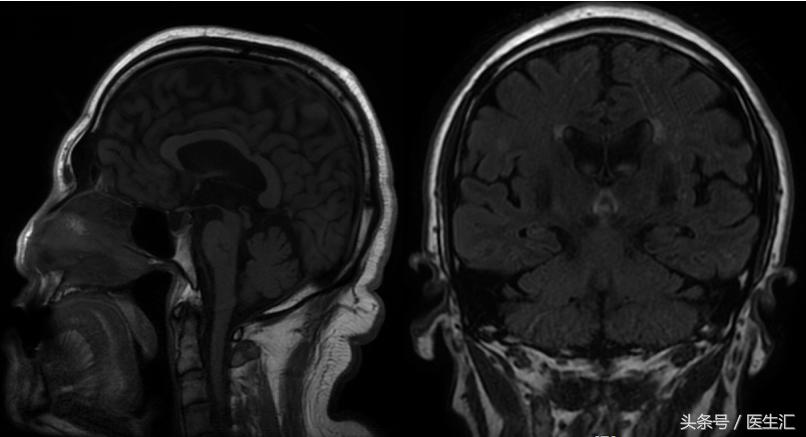

影像检查

进行性核上性麻痹-帕金森型